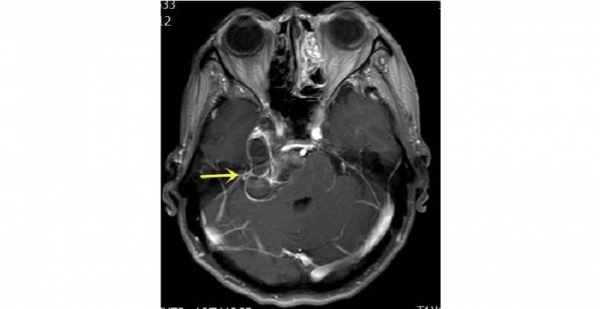

大腦是人體最精密最復雜,也是最重要的器官,而橋小腦角區(qū)更是大腦的主陣地,它集中了聽神經、面神經、三叉神經等重要結構,毗鄰控制心跳與呼吸的腦干,是大腦的的“生命禁區(qū)”。因其位置特殊,腫瘤又與橫竇關系密切,稍有不慎可引起大出血,隨時面臨生命危險,想要手術成功,張教授需要挑戰(zhàn)這個難題。

經過精心的準備,5月10日,神經外科團隊與麻醉手術科醫(yī)護團隊精誠協(xié)作,歷時4個小時,腫瘤順利全切,相鄰的神經血管保護完全,手術順利完成。術后,魁大媽身體狀況一切良好,手術取得滿意的效果。